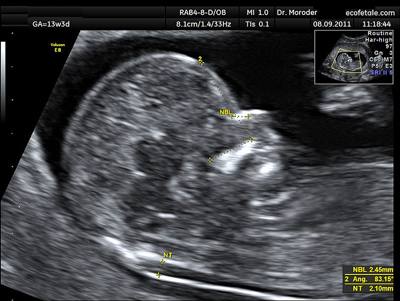

Nekplooi

De nekplooi is een laagje vocht onder de huid in de nek van je baby. Ook gezonde kinderen hebben dit laagje. Hoe dikker de nekplooi, hoe groter de kans dat je kindje het Downsyndroom heeft. Een ‘verdikte nekplooi’ heeft een dikte van meer dan 3,5 millimeter. Een baby met een verdikte nekplooi, hoeft niet per se het Downsyndroom te hebben. Wel betekent het dat het kindje een verhoogde kans op het Downsyndroom heeft, evenals een verhoogde kans op hartafwijkingen en andere chromosomale afwijkingen.